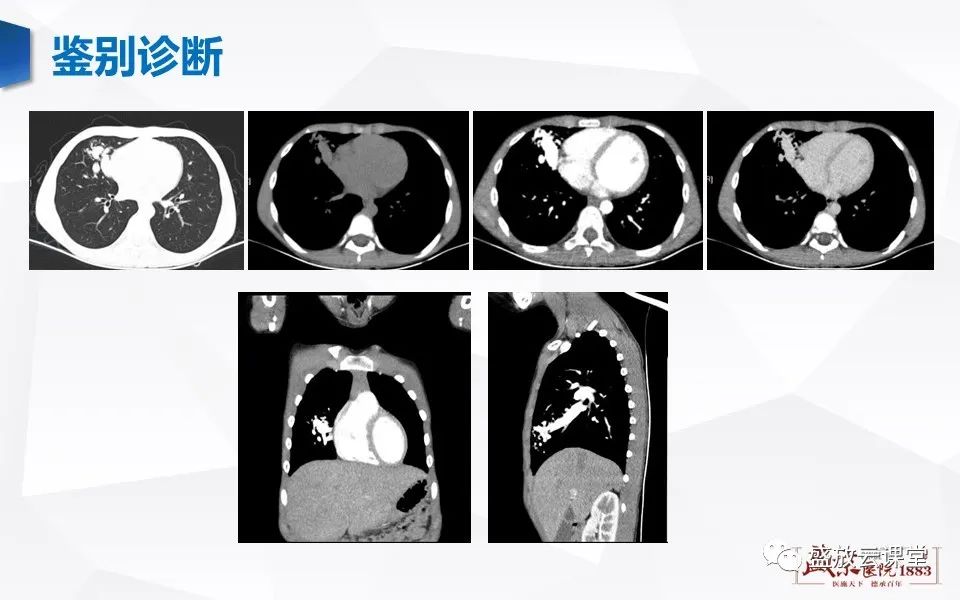

【病例】肺错构瘤 VS 肺硬化性血管瘤